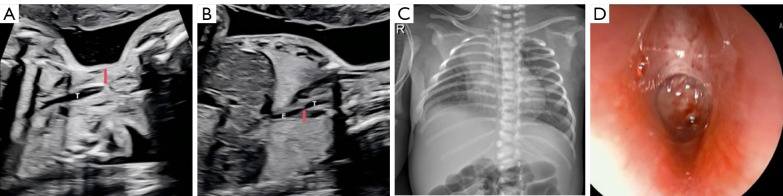

Diagnosis of fetal laryngotracheal atresia combined with tracheoesophageal fistula via prenatal ultrasound: a case description.

产前超声诊断胎儿喉气管闭锁合并气管食管瘘1例。